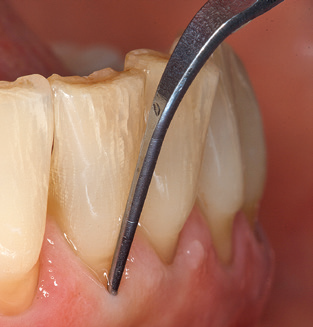

The current working concept for SPT

Updating the patient’s medical history is an important aspect of SPT and should occur at least once per year. It helps the dental team to identify and document any new risk factors. Especially when a patient is treated over many years, it is important to establish whether patient-specific and general health risk factors have changed. This primarily concerns a heightened risk as a result of diabetes, but other general conditions (cardiovascular disease and neoplasia) can also produce a modified risk profile as a result of the treatment performed and medication administered. Accordingly, updating the medical history as part of SPT is very important, as a modified risk profile may trigger the need to adapt the treatment interval. In the next step, it is important to afford the diagnostics due attention. Whilst instruments are a central aspect of SPT, findings and their documentation must never be neglected. The periodontological findings are essential for a good diagnosis; increases in the pocket depths and the BOP index are clear indicators of advancing periodontal and peri-implant disease. As such, the team should not shy away from probing implants too, with the aim of gathering the requisite data. At the same time, it is important to use periodontal probes with millimetre markings. Metallic probes have already been used for determining pocket depths around natural teeth for decades. In the case of implants, the challenge of recording correct and reproducible pockets depths is even greater. As the discrepancy between the implant diameter and the contour of the superstructure regularly results in overcontouring of the superstructure, flexible probes which still feature millimetre markings are a sensible solution for measuring pocket depths around implants (e.g., Colorvue Kit PCV11KIT6, HuFriedy; Fig. 4).